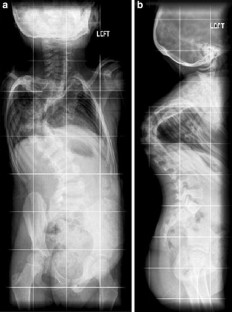

In this Grand Round, we present the case of a 7-year-old girl with a severe scoliosis and thoracic insufficiency syndrome (TIS). 3D CT reconstruction imaging demonstrated a mixed picture of fusion and segmentation abnormalities. A marked kyphoscoliosis was demonstrated at the thoraco-lumbar junction. Via a left thoracotomy, anterior excision of intervertebral discs was performed together with, interbody fusion, and in situ stabilisation of the kyphosis with double allograft (femur) strut grafts.